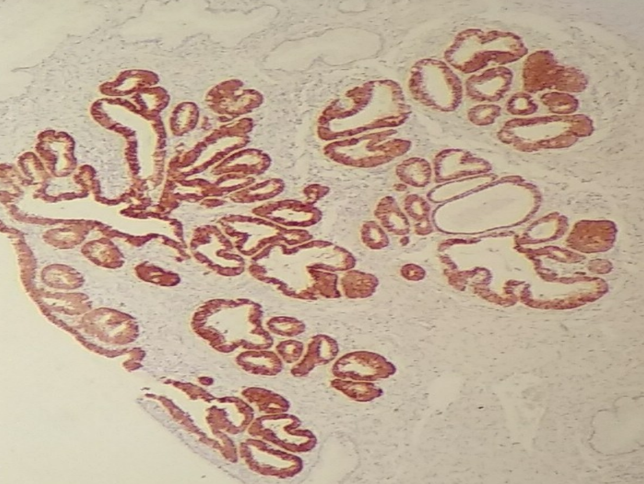

Inmunohistoquímica

Se basa en la utilización de anticuerpos que se unen específicamente a una sustancia (antigeno) que se quiere identificar en la lesión.